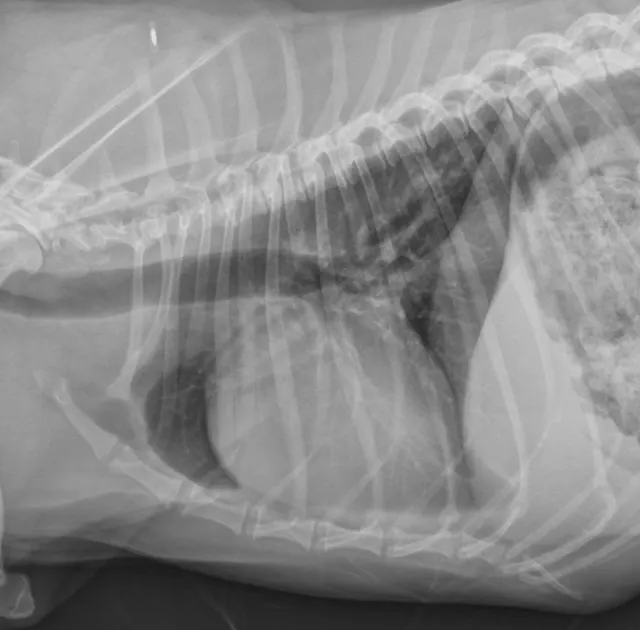

Right lateral (Figures 1 and 2) and dorsoventral (Figures 3 and 4) radiographs of 2 dogs with grade 3/6, holosystolic, left apical murmurs. Dog 1 (Figures 1 and 3) has mild left atrial enlargement; dog 2 (Figures 2 and 4) has a severely enlarged left atrium.